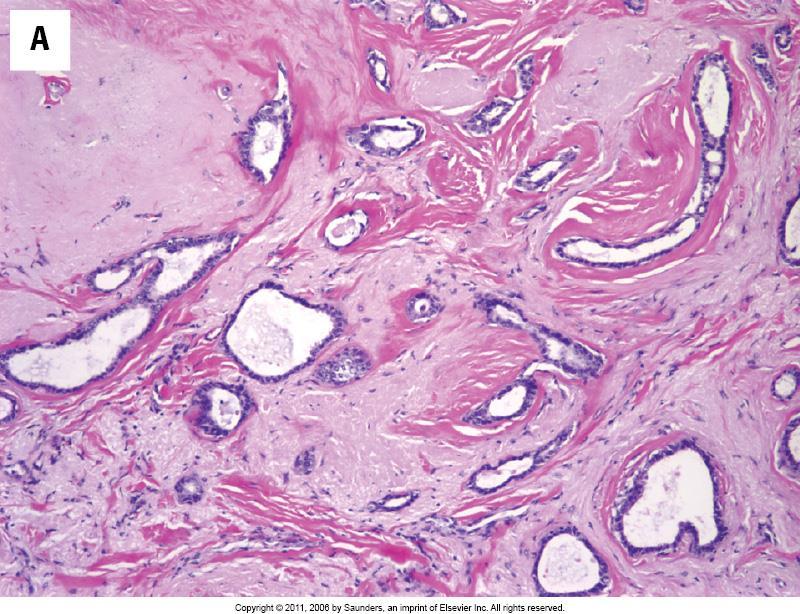

Pure tubular carcinomas ± 5% of all invasive breast carcinomas Bland tubules with angulated outline and open lumen Haphazard tubular arrangement in a desmoplastic stroma SMM and p63 negative Good prognosis compared to other invasive ductal carcinoma

ΔΔ Sclerosing adenosis

Central fibroelastosis Entrapped benign ducts Associated epithelial hyperplasia <1cm radial scar >1cm complex sclerosing lesion Increased risk for subsequent breast cancer development

ΔΔ Tubular carcinoma (myoepithelial markers are helpful)